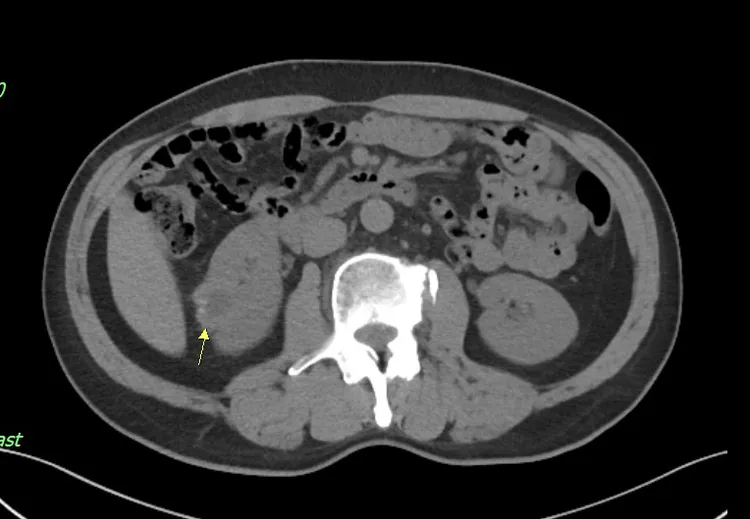

治療前12.5公分腫瘤。奇美醫院提供